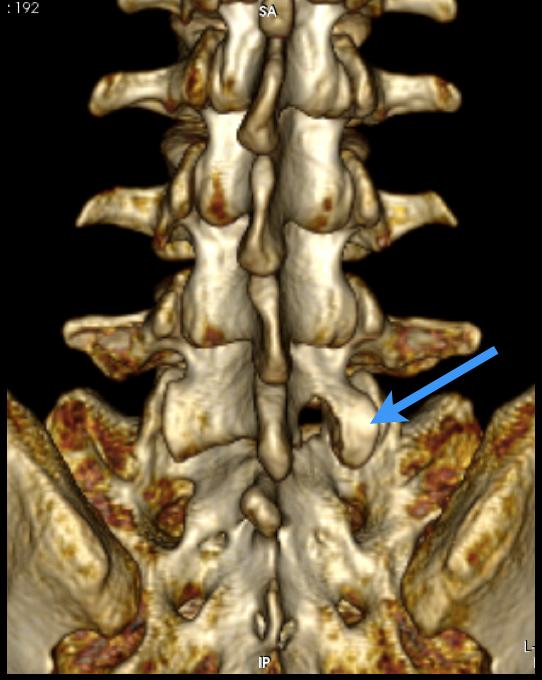

Diagnóstico: Fractura Traumática de Vertebras Torácicas T11 y T12. Clasificación AO: C3.N3.M1, TLICS: 9 puntos, ASIA B

Tipo de Cirugía: Reconstrucción Espinal Avanzada, mediante Instrumentación transpedicular T9-T10 a L1-L2, con descompresión medular microquirúrgica T11-T12

Fecha de la cirugía: Diciembre 23 del 2017

Me accidenté el 22 de Diciembre del 2017 cayéndome de una altura de 3 metros rompiéndome mi columna y poniéndome muy grave de salud. Fui operado por el Dr. Rodrigo Lorenzana restaurándome mi columna con tornillos transpediculares, barras y un travesaño, ya que estuve internado durante varios días. Recibí un trato bueno, profesional y amable por parte del Dr. Lorenzana. Hasta la fecha me sigue atendiendo en consultas con el mismo trato profesional y amable.